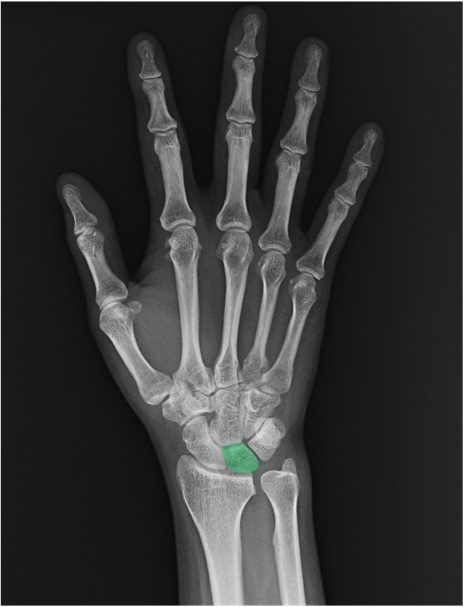

月状骨(lunate)の手関節レントゲン画像における正常解剖

舟状骨(scaphoid)

三角骨(triquetrum)

橈骨(radius)

尺骨(ulna)

尺骨茎状突起(ulnar styloid process)

CM関節(carpometacarpal joint)

IP関節(interphalangeal joint)

MP関節(metacarpophalangeal joint)

PIP関節(proximal interphalangeal joint)

DIP関節(distal interphalangeal joint)